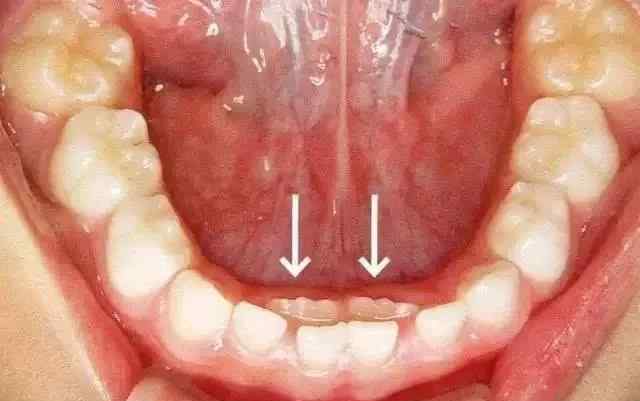

6岁左右,大部分孩子的下切牙松动脱落,新牙会沿着原来的乳牙萌出。然而,越来越多的儿童乳牙正在萌出,这就是我们所说的“双排牙”现象。

如因乳牙滞留造成“双排牙”,家长应尽快带孩子去牙科医院拔除滞留的乳牙。

乳牙拔除的牙根会因为恒牙萌出位置的不同而有不同程度的吸收,有些可能根本就没有吸收。异位恒牙会随着颌骨发育和外力调整而逐渐移动。如果所有儿童恒牙长出来后仍然存在牙齿排列不均匀等问题,需要选择合适的时间进行正畸治疗。一般矫正的最佳年龄为12~14岁。